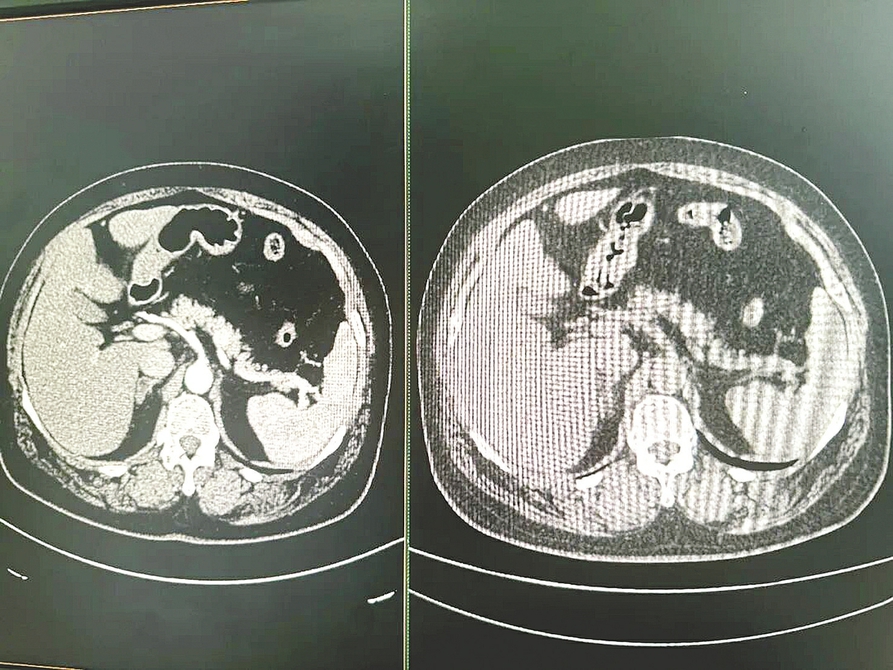

家住浙江宁波的57岁邱先生对《每日经济新闻》记者回忆称:2025年8月,其因患糖尿病,在宁波大学附属人民医院做了一次常规检查,并拍摄了腹部平扫CT。午饭时,他接到医院打来的电话:“你的胰腺可能有点问题,需要进一步检查。”电话那头是该院的副院长、肝胆胰外科主任医师朱柯磊。

据邱先生介绍,医生在电话里并未明说是什么问题,但其心里清楚“肯定不是好消息”。其迅速做了增强核磁共振检查(MRI),并于第二天接受了微创手术。朱柯磊医生还告诉邱先生,“你和乔布斯得了一样的病,但你比乔布斯幸运得多”。

据《每日经济新闻》记者了解,救了邱先生一命的,是阿里巴巴达摩院研发的胰腺癌AI早筛模型——PANDA。该AI模型从邱先生那张看似并无异常的平扫CT影像中,捕捉到了癌变的迹象。

朱柯磊医生向《每日经济新闻》记者解释称,临床上用于腹部检查的CT分为平扫CT和增强CT。增强CT需患者注射造影剂,可以更清晰地显示器官和病灶,但成本较高、操作相对复杂,且造影剂可能引发过敏反应,通常仅用于有明确诊断目的的病人。

然而,由于胰腺与周围组织对比度低,在平扫CT影像上难以看清。微小的早期肿瘤更是如同“隐形”一般,极难被人眼发现。因此,“平扫CT无法用于早期胰腺癌筛查”曾是放射科的普遍共识。

为此,达摩院医疗AI肿瘤早筛和影像智能相关团队想出了一个“迂回战术”。他们收集了数千例胰腺癌患者的数据,先由有经验的医生在对比度清晰的增强CT影像上精确标注出病灶位置,再利用图像配准技术,将这些标注信息精准地“映射”回同一位患者的平扫CT影像上。

据《每日经济新闻》记者了解,经过近两年训练,PANDA模型学会了识别平扫CT影像上那些微妙的密度变化、纹理异常和结构扭曲——这些特征虽难以被肉眼察觉,却是早期胰腺癌的蛛丝马迹。

2023年11月,公开发表在国际顶尖期刊《自然·医学》上的论文数据显示,PANDA模型筛查胰腺癌的敏感性(识别出有病灶的能力)达到92.9%,特异性(排除无病灶者的能力)高达99.9%。这意味着,AI不仅能“揪出”绝大多数病患,还能避免大规模的“虚假报警”。